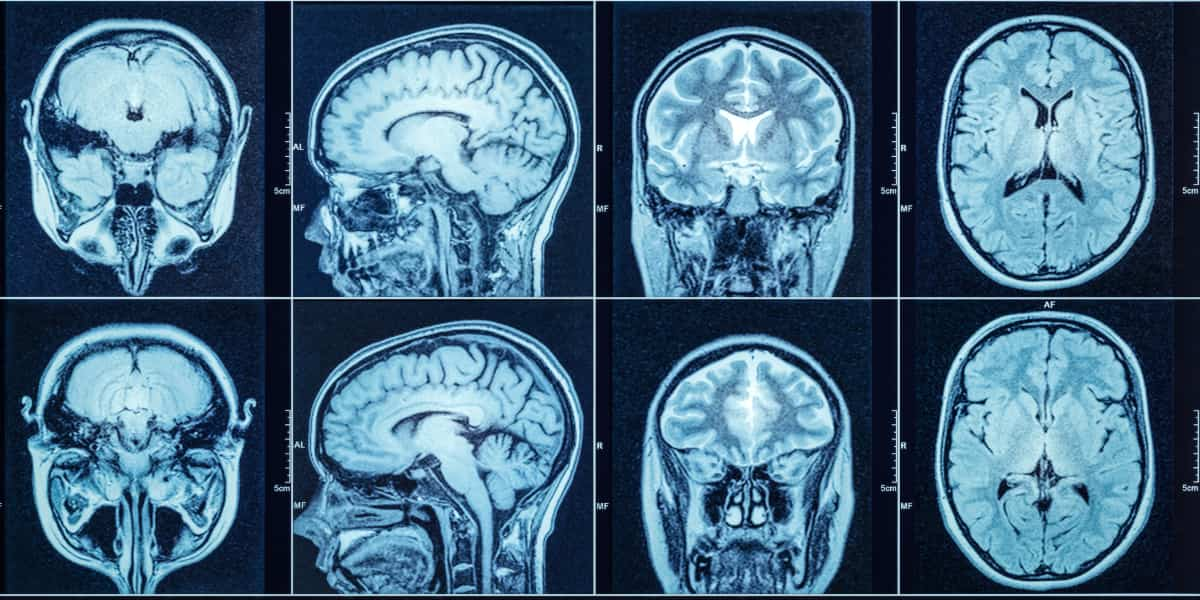

MRI: The Gold Standard for Soft Tissue

Unlike the others, an MRI uses powerful magnets and radio waves, not radiation, to generate highly detailed images of the body’s internal structures. An MRI is usually an outpatient test that is ordered by your primary care doctor. An MRI is the only way to clearly see:

- Herniated or bulging discs in the spine

- Torn ligaments (like an ACL or rotator cuff)

- Nerve impingement (pinched nerves)

- Deep tissue bruising and inflammation